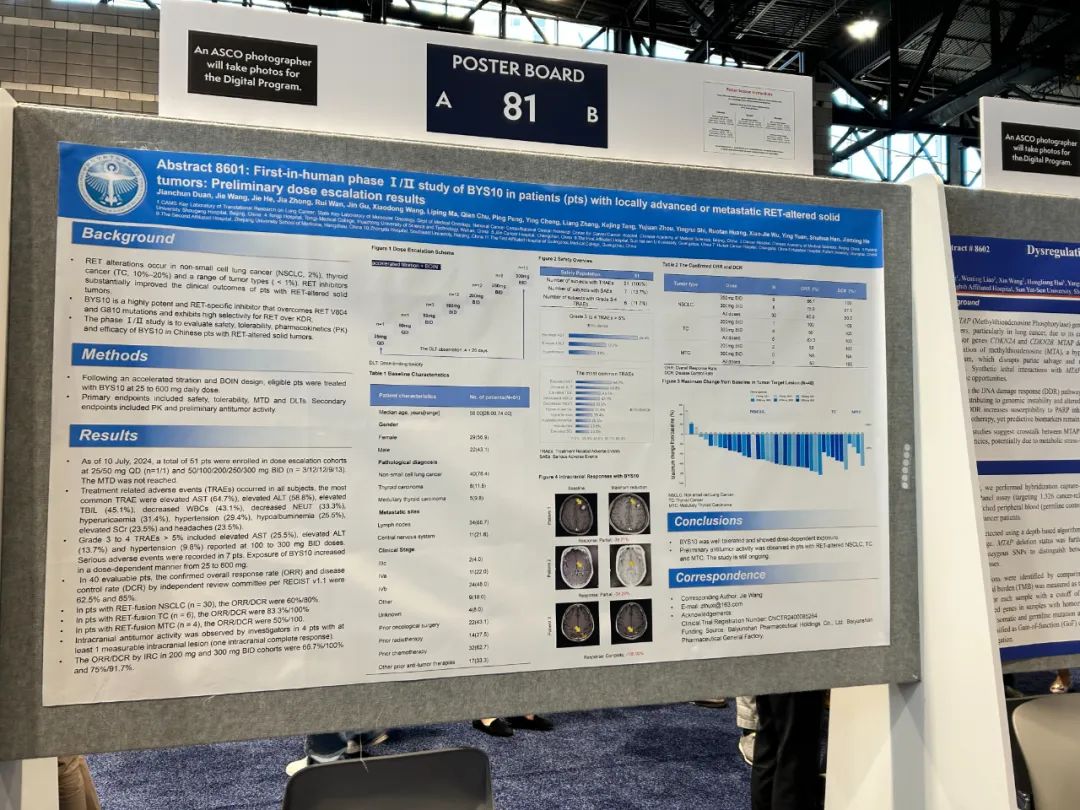

иҜҘв… /в…Ўжңҹз ”з©¶е…ұзәіе…Ҙ51дҫӢRETзӘҒеҸҳе®һдҪ“зҳӨжӮЈиҖ…�пјҢпјҢпјҢпјҢ�пјҢ�пјҢеҮӯиҜҒеҠ йҖҹж»ҙе®ҡе’ҢBOINи®ҫи®Ў�пјҢпјҢпјҢпјҢ�пјҢ�пјҢеҲҮеҗҲжқЎд»¶зҡ„жӮЈиҖ…жҺҘеҸ—BYS10жІ»з–—�пјҢпјҢпјҢпјҢ�пјҢ�пјҢйҖҗж—ҘеүӮйҮҸдёә25иҮі600 mg�гҖӮгҖӮгҖӮгҖӮ�гҖӮз ”з©¶зҡ„дё»иҰҒз»ҲзӮ№еҢ…жӢ¬жё…йқҷжҖ§гҖҒиҖҗеҸ—жҖ§гҖҒжңҖеӨ§иҖҗеҸ—еүӮйҮҸпјҲMTDпјүе’ҢеүӮйҮҸйҷҗеҲ¶жҖ§жҜ’жҖ§пјҲDLTпјү�гҖӮгҖӮгҖӮгҖӮ�гҖӮж¬ЎиҰҒз»ҲзӮ№еҢ…жӢ¬иҚҜд»ЈеҠЁеҠӣеӯҰпјҲPKпјүе’Ңиө·жәҗжҠ—иӮҝзҳӨжҙ»жҖ§[1]�гҖӮгҖӮгҖӮгҖӮ�гҖӮ

йҳ»жӯў2024е№ҙ7жңҲ10ж—Ҙ�пјҢпјҢпјҢпјҢ�пјҢ�пјҢ2дҫӢжӮЈиҖ…еҲ’еҲҶеңЁеүӮйҮҸйҖ’еўһиЎҢеҲ—дёӯжҺҘеҸ—25mg/QDе’Ң50mg/QDеүӮйҮҸжІ»з–—�пјҢпјҢпјҢпјҢ�пјҢ�пјҢе…¶дҪҷ49дҫӢжӮЈиҖ…еҲ’еҲҶжҺҘеҸ—50mg/BIDпјҲn=3пјүгҖҒ100mg/BIDпјҲn=12пјүгҖҒ200mg/BIDпјҲn=12пјүгҖҒ250mg/BIDпјҲn=9пјүгҖҒ300mg/BIDпјҲn=13пјүжІ»з–—[1]�гҖӮгҖӮгҖӮгҖӮ�гҖӮ

еӣҫ1.з ”з©¶и®ҫи®Ў